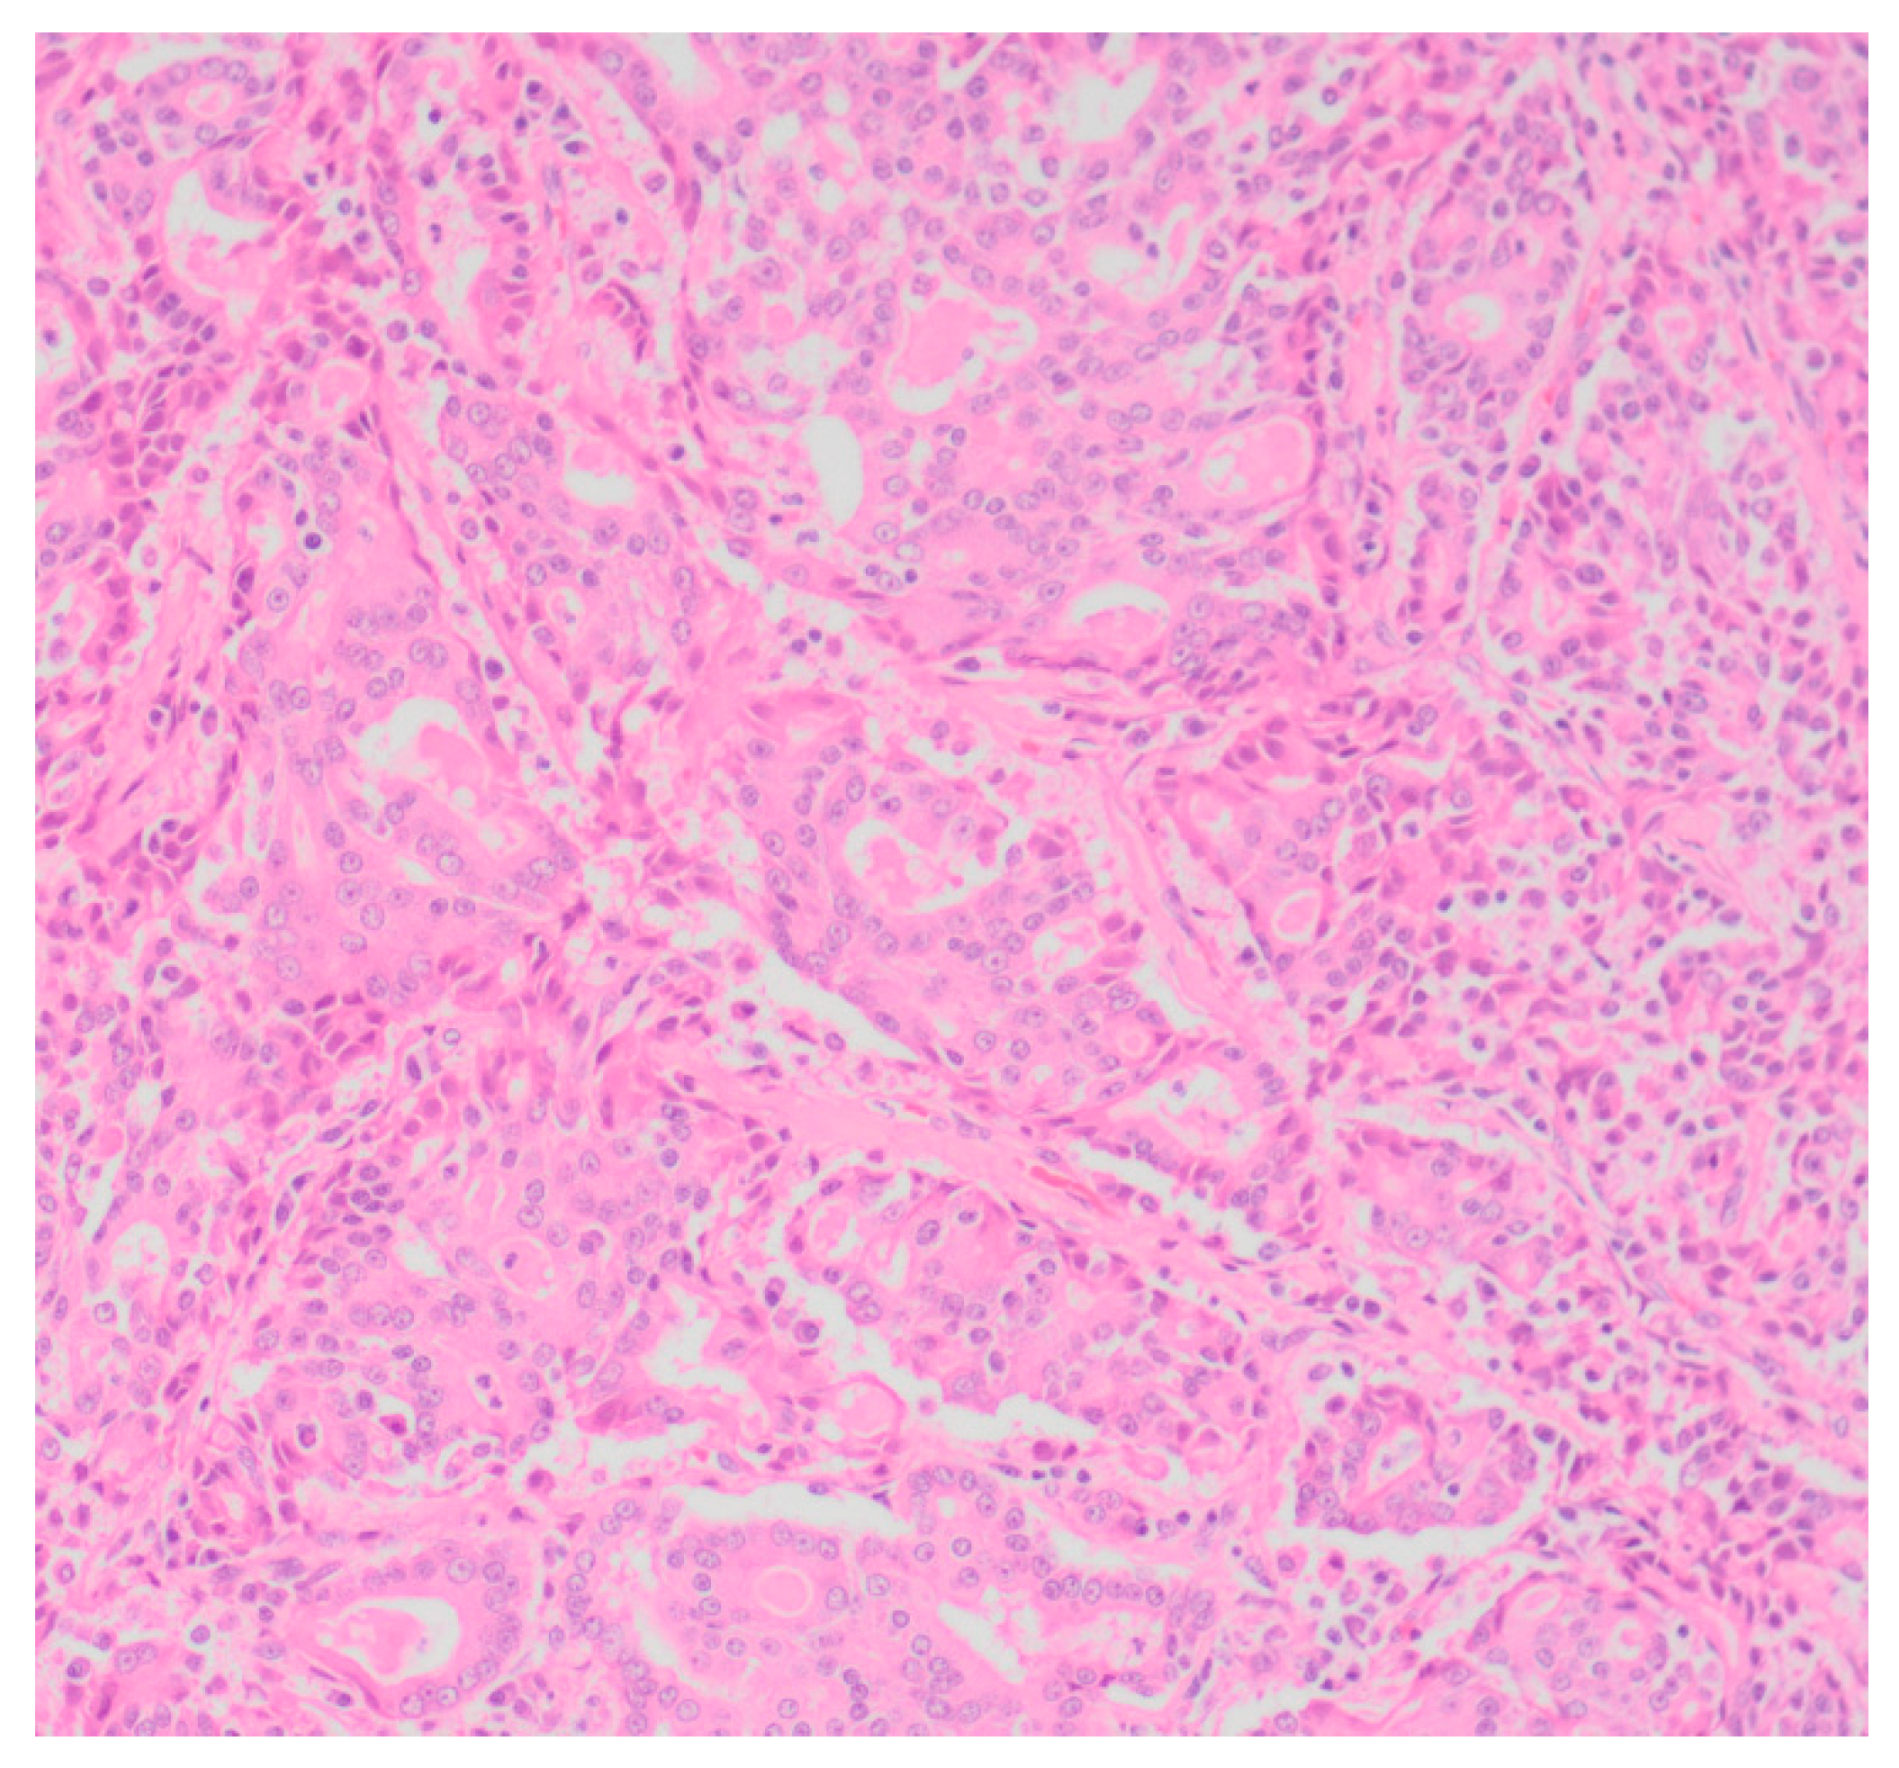

Sixty-five (87.8%) of the tumors examined histologically were classified as malignant, while 9 (12.2%) were classified as benign. All MGTs histologically identified as malignant included at least three cellular or nuclear criteria of malignancy (Figure 1 and Figure 2). Histological evidence of peri-tumoral (n = 6) and lymphatic (n = 4) invasion was identified in 10 malignant tumors, while randomly distributed areas of necrosis within the neoplasm were observed in 16 malignant tumors.

Figure 1. Tubular carcinoma (Grade III), mammary gland, canine (low power).